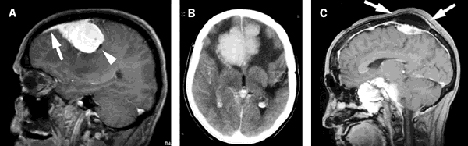

Radiographic signs of meningiomas

A: Tail sign: tapering dural thickening (arrow) due to direct tumor involvement or reactive change in the dura, is a highly characteristic sign of meningioma; note also the small reactive arachnoid cyst, reflecting the extraaxial site of this lesion (arrowhead). B: Reactive cerebral white matter changes. C: Bony reactive changes: reactive bone sclerosis, reflected in the increased vault thickness (arrows) is seen most commonly in patients with multiple meningiomas associated with neurofibromatosis type 2; invasive tumors such as these can cause problematic extracranial facial masses. Reproduced with permission from: Whittle, IR, Smith, C, Navoo, P, Collie, D. Meningiomas. The Lancet 2004; 363:1536. Copyright ©2004 Elsevier.